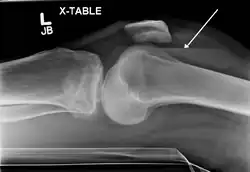

Lipohemarthrosis due to a tibial plateau fracture -